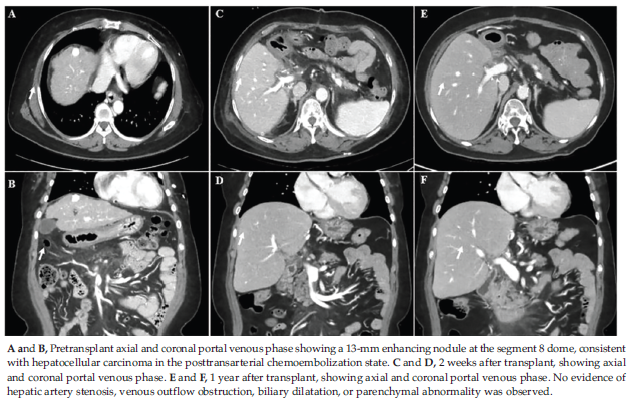

The recipient was a 66-year-old woman with hepa-titis B-related cirrhosis and hepatocellular carcinoma (mUICC stage I). Preoperative computed tomog-raphy (CT) demonstrated a cirrhotic liver with a 13-mm LR-5 hepatocellular carcinoma lesion at the dome of segment 8, previously treated with transarterial chemoembolization (Figure 1, A and B). The donor was her 42-year-old daughter. Donor volumetry indicated a whole liver weight of 1185 g, with right and left lobes measuring 770 g and 415 g, respectively, leaving a remnant of 35%. The estimated graft-to-recipient weight ratio was 1.13.

Follow-up CT scans at 2 weeks and 1 year showed no graft-related abnormalities (Figure 1, C-F). The patient was discharged on POD21, and the donor recovered uneventfully. During follow-up, isoag-glutinin titers rebounded to IgG 1:128 and IgM 1:4 within the first month but declined thereafter.

At 2 years, titers had stabilized at IgG 1:32 and IgM 1:2 (Figure 3). Liver function tests and tacrolimus trough levels remained within target ranges (Figure 4). Hematologic indices and C-reactive protein, assessed alongside perioperative transfusions, showed no significant abnormalities (Figure 5). Because laboratory parameters were stable and CT scans revealed no biliary dilatation or vascular abnormalities, neither liver biopsy nor magnetic resonance cholangiopancreatography was performed. No AMR, graft dysfunction, or infectious complica-tions occurred during the 2-year posttransplant obser-vation period.

Figure 1. Representative Computed Tomography Images Before and After ABO-Incompatible Living Donor Liver Transplant